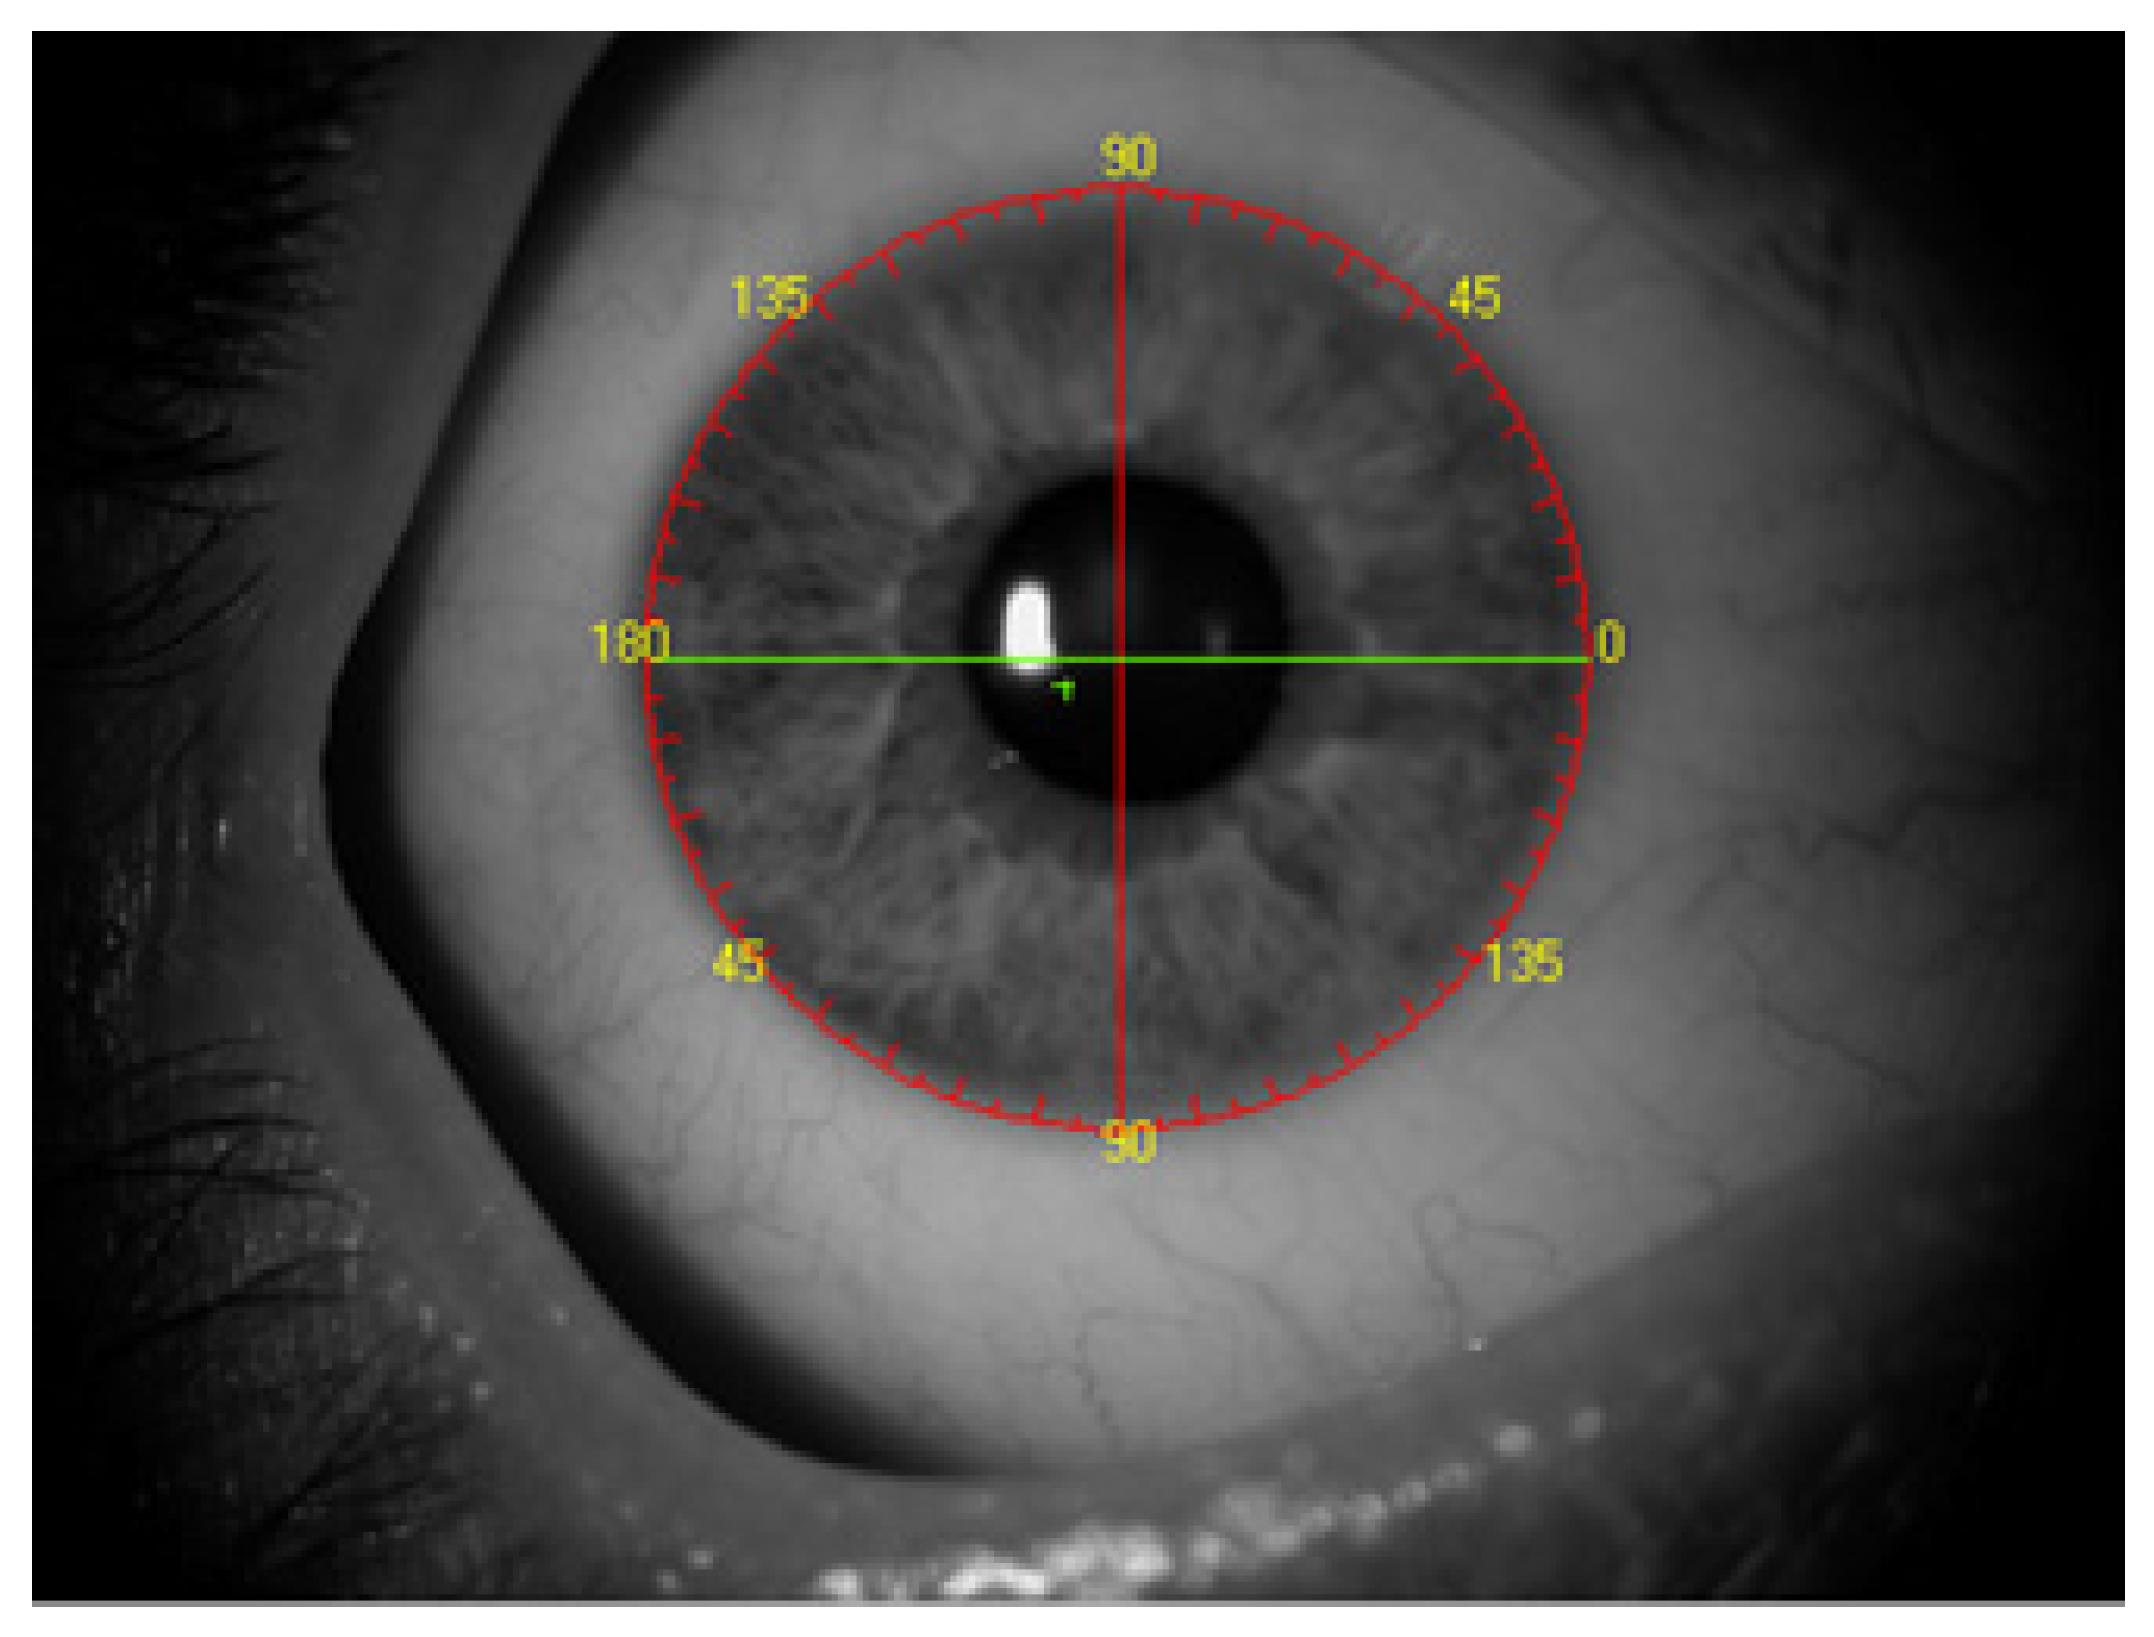

Major changes have been occurring in the field of preoperative preparation and the performance of procedures for the use of toric intraocular lenses for the past several years. The changes are aimed at obtaining the best possible postoperative visual acuity, which in turn leads to an increasing use of toric lenses, even at low astigmatism values [1,2]. The introduction of such lenses has led to the creation of a diverse set of instruments to support surgeons in determining the axis of implanted lenses. There are numerous manual methods for determining the axis of implanted intraocular lenses. Automatic systems for determining the axis of the implant are becoming increasingly common. Such methods involve overlaying an image on the eye in real time to guide the incision site and capsulorhexis and they use the Technischer Ausschuss für BrillenOptik (TABO) scale to facilitate axial positioning of the intraocular lens in the eyeball [3,4] (Figure 1).

Figure 1. TABO scale.

Figure 2. Region of interest of the INTEGRA system. Area indited to analyze is outside red circle and limited by green line.